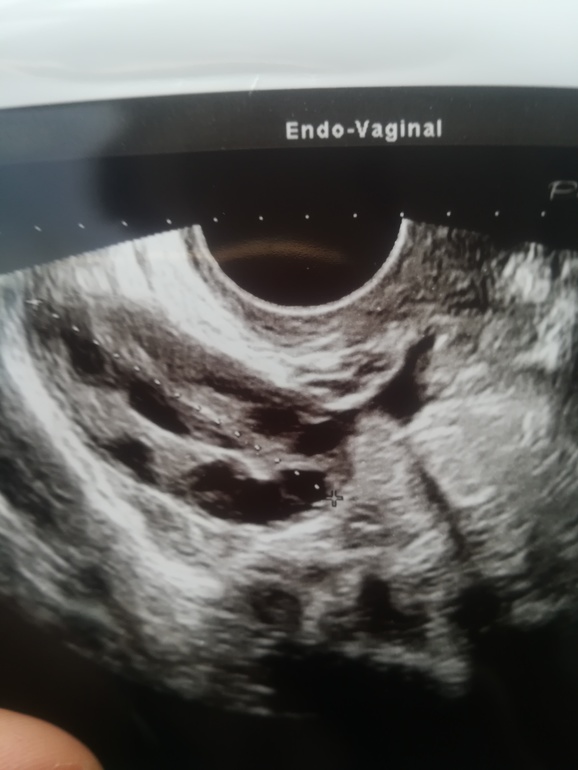

Девочки, кто разбирается в фото? Вот фото 2х яичников . Что вы на них видите? Жт есть ?

Похоже больше на сдувающийся фолликул. Так как форма какая-то расплывшаяся, нечеткая. А ЖТ по узи немного иначе выглядит, оно круглое(овальное) больше серого цвето, с сосудистыми кольцом и кровотоком. Вам на узи должны были это сказать.

На УЗИ сказали дф, но жидкость 15 мл в позадиматочном. Вот поэтому спросила. Сдувпбщийся не может быть, т.к в пн он был 12*15, а сейчас 16*18 .

Странные узисты, как можно не понять дф или жт. Я сужу по фото, так выглядит ДФ, а у вас что-то непонятное.

У фолликула роные границы.тут больше на жт похоже.И персистирующий фоллик(нелопнувший)выглядит по доугому.Я в живую это видела у себя!!Там как ровная капсулка а внутри уже искажаться начинает..

Просто по картинке сказать что это ДФ или ЖТ не возможно. Нужно кровотоки смотреть. ЖТ имеет васкуляризацию.